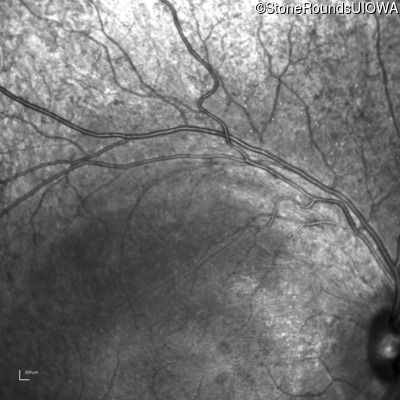

Infrared Fundus Photograph - Left - 20/25

Exemplar